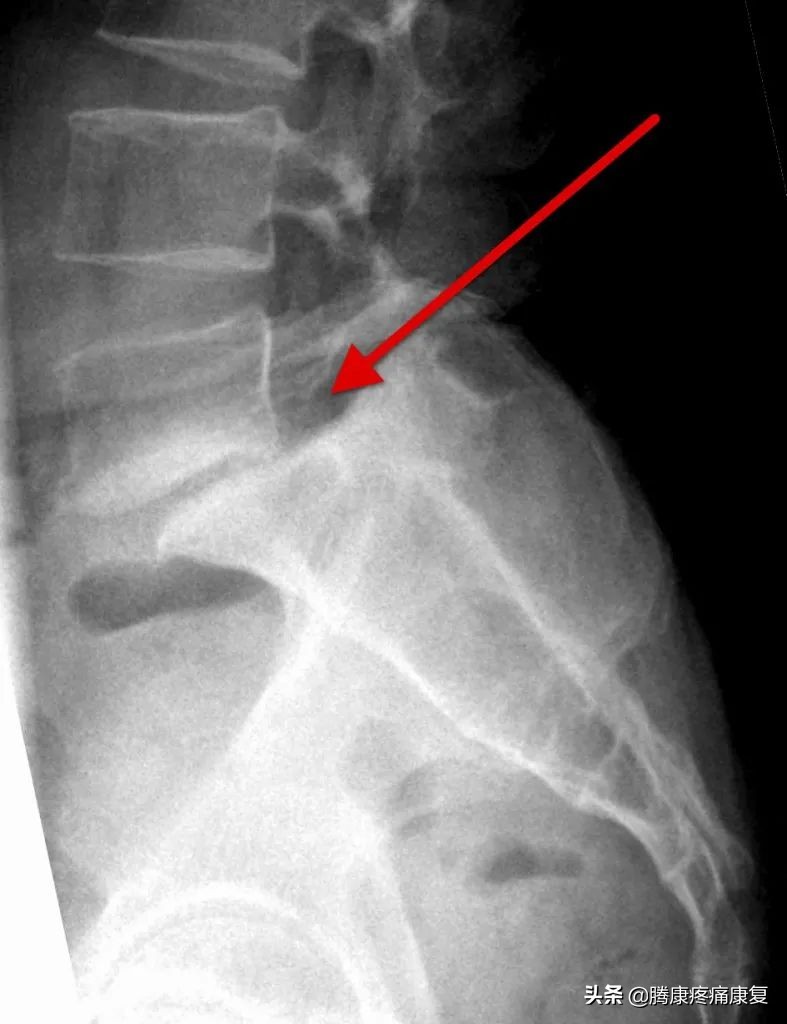

腰椎滑脱是一种比较常见的疾病,是指其中一节段椎体与下方椎体向前滑动或脱离。

脊椎滑脱有5种类型包括: 发育不良,峡部裂,退行性病变,创伤性病变和病理性病变 。其中退行性腰椎滑脱是最常见的类型,好发于20~50岁的成年人群,常见于L4~L5脊椎段,占总发病人群的60%以上。在退行性脊椎滑脱症中,椎体的前滑是由于正常老化过程中发生的脊柱退行性变化引起的。

这张图片显示了腰椎是如何随着时间的推移而退化的:

MRI/CT扫描可发现脊椎滑脱